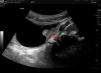

We present the case of a boy aged 6 years with chance finding of an intravesical mass in a follow-up ultrasound scan conducted 5 years after ureteral reimplantation surgery for vesicoureteral reflux. As seen in Fig. 1, the sonogram showed a hyperechoic parietal lesion measuring 10 × 5 mm and with well-demarcated borders, as well as evidence of vascularization in colour Doppler imaging. The scan also detected a second lesion of similar characteristics. A cystoscopy was performed, leading to detection and resection by diathermy of 4 lesions, including the 2 previously identified in the left inferolateral and posterior surfaces of the bladder and 2 smaller lesions located in the dome. Fig. 2 shows the largest one, located in the left inferolateral surface. The final histological diagnosis was nephrogenic adenoma of the bladder. Fig. 3 presents histological examination images including haematoxylin-eosin and immunohistochemistry staining. The patient remains asymptomatic and has not experienced recurrence one year after the intervention. On occasion, the routine follow-up of paediatric urologic patients gives rise to chance findings, and it is important to be aware of certain infrequent diseases that need to be included in the differential diagnosis. Nephrogenic adenoma is a metaplasia of the urothelium that may develop anywhere in the urinary tract.1 It is a benign condition, and it has been hypothesised that local inflammation or repetitive trauma could play a role in its development.2 It may be asymptomatic or manifest with dysuria, haematuria or recurrent urinary tract infection. The standard of care is complete endoscopic excision, and follow-up of the patient is required to detect potential recurrences.3